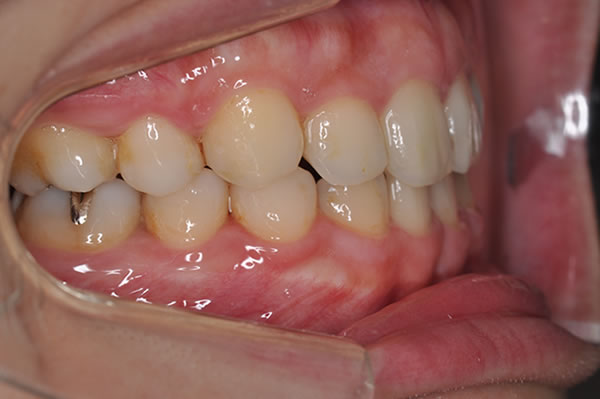

上顎前突症の治療例

上顎前突症(出っ歯)の矯正症例 ケース01

上顎前突症(出っ歯)の矯正症例 ケース02